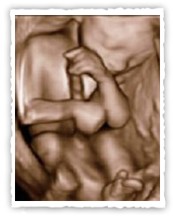

Ab der 23. Schwangerschaftswoche ergeben sich bei geeigneter Lage des Kindes

sehr schöne Bilder.

Ideal für die Bilderstellung ist der Zeitraum von der 23. bis zur 32. Schwangerschaftswoche.

Aufnahme in der 23. Schwangerschaftswoche (links)/ 32. Schwangerschaftswoche (rechts)